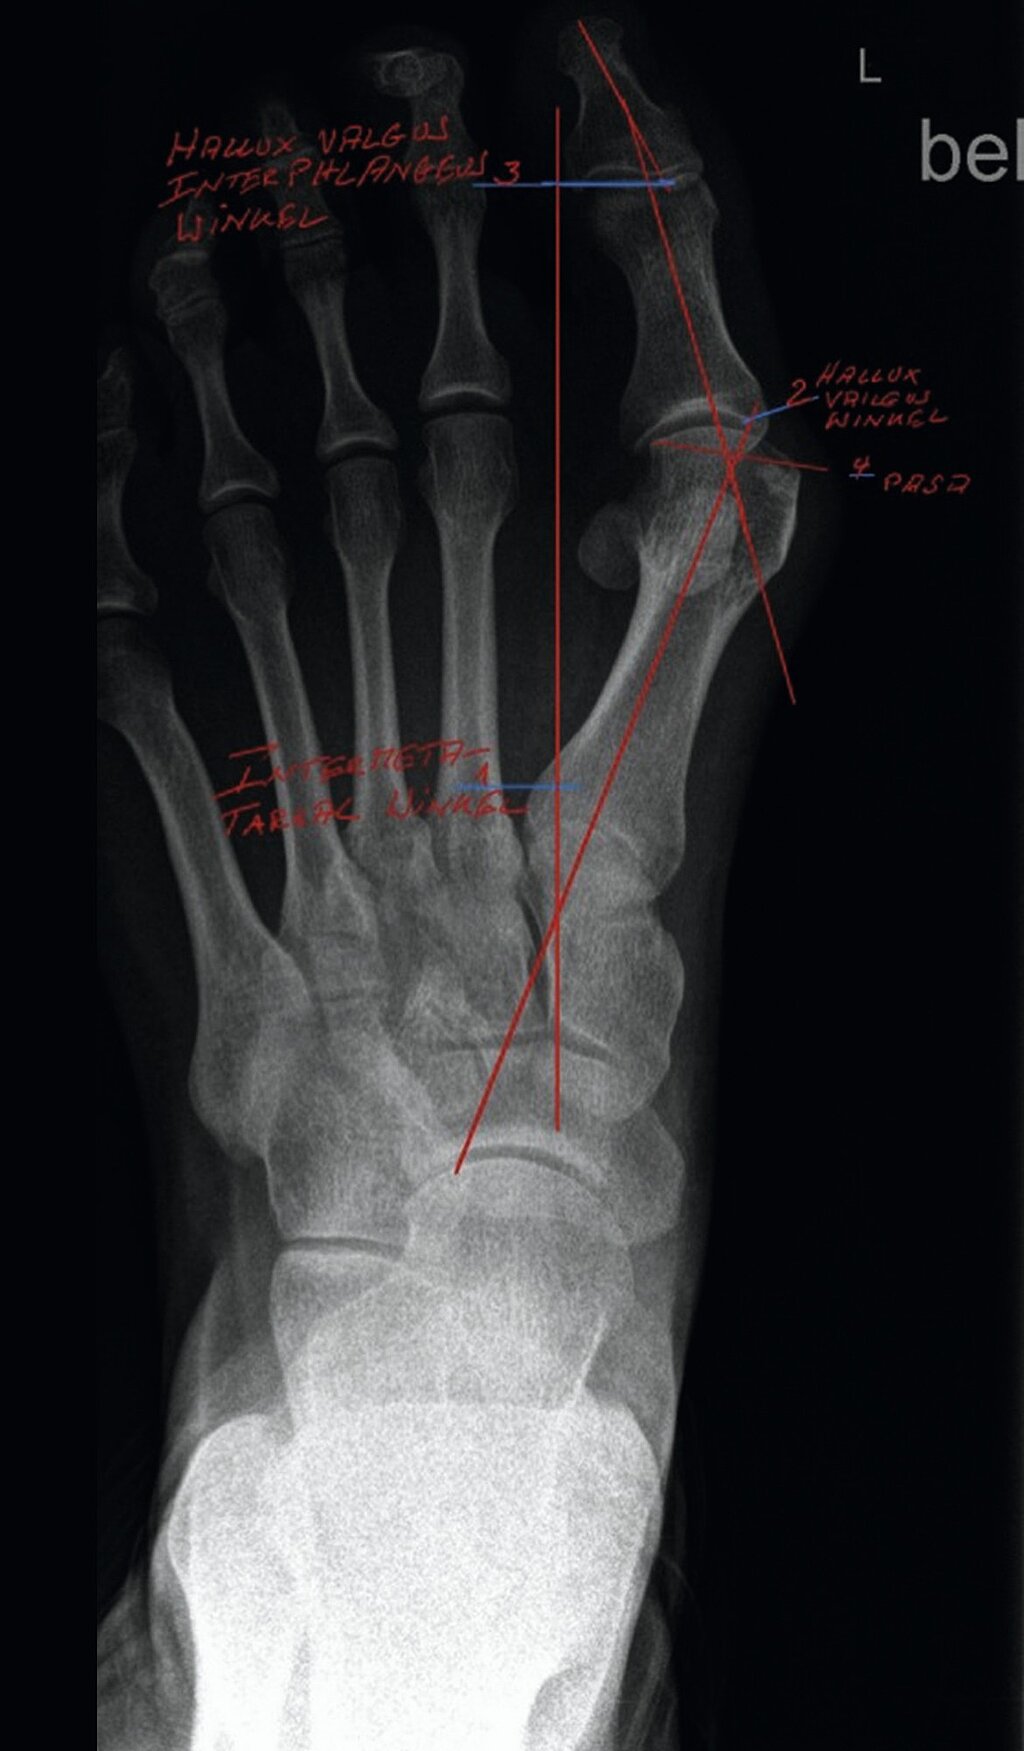

Die wichtigste bildgebende Diagnostik ist nach wie vor die Röntgenaufnahme des Fußes unter Belastung im a.p. (Abb. 2) und seitlichen Strahlengang sowie eine Aufnahme in 45°. Im Rahmen dieser Untersuchung werden der sog. Hallux valgus-Winkel, Intermetatarsalwinkel, Kopf-Gelenkwinkel sowie der Metatarsale-Index ermittelt [2,3]. Weiterhin wird die Knochen- und Gelenkstruktur zur Abklärung z. B. einer Arthrose (Gelenkverschleiß), Osteoporose, Osteonekrose, Osteoarthropathie etc. beurteilt. Als weitergehende Verfahren stehen die Kernspintomographie, die Computertomographie, digitale Volumentomographie (DVT) und/oder die Szintigraphie zur Verfügung.

Gemäß der neuen Leitlinie Hallux valgus wird die Fehlstellung nur noch in zwei Schweregrade eingeteilt:

- Leicht/moderat: Intermetatarsalwinkel < 18° und Hallux valgus Winkel < 40°

- Schwer: Intermetatarsalwinkel > 18° und Hallux valgus Winkel > 40°

Die Metaanalyse zeigte eine mittlere Verbesserung des Intermetatarsalwinkels (IMA) um 7,3°, des Hallux-valgus-Winkels (HVA) um 18,9° (am besten mit MIS der 3. Generation: 21,2°) und des AOFAS-Scores um 33,8 Punkte. Signifikante Gruppenunterschiede zeigten sich nur beim Hallux-valgus-Winkel. Die präoperativen Werte hatten maßgeblichen Einfluss auf das Korrekturergebnis. Basierend auf den Ergebnissen wird eine binäre Einteilung der Deformität (leicht/moderat vs. schwer) für die Therapieplanung empfohlen. Die frühere Unterteilung in leicht und moderat ist lt. Leitlinie operativ nicht relevant.